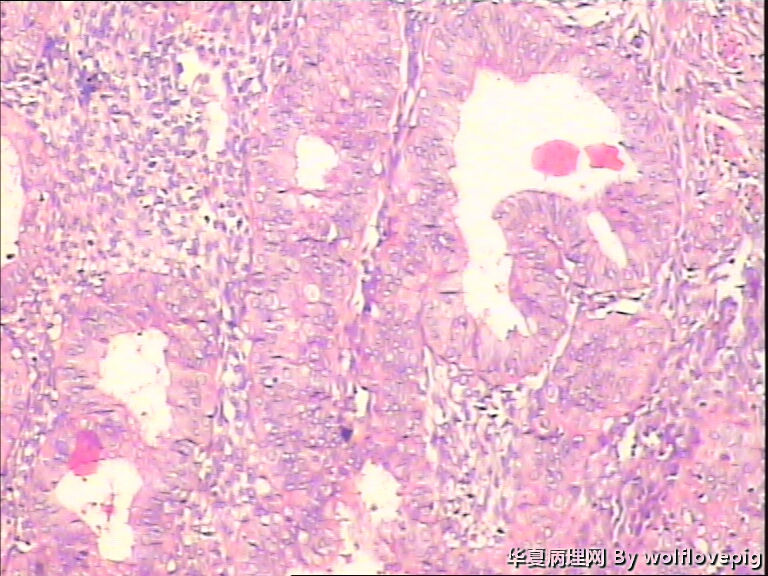

求助,子宫内膜!

48y

子宫内膜复杂性非典型增生(有没有癌变,待制作优良的切片再诊断吧)。

复杂性非典型增生

复杂性非典型增生(EIN)

子宫内膜复杂性非典型增生